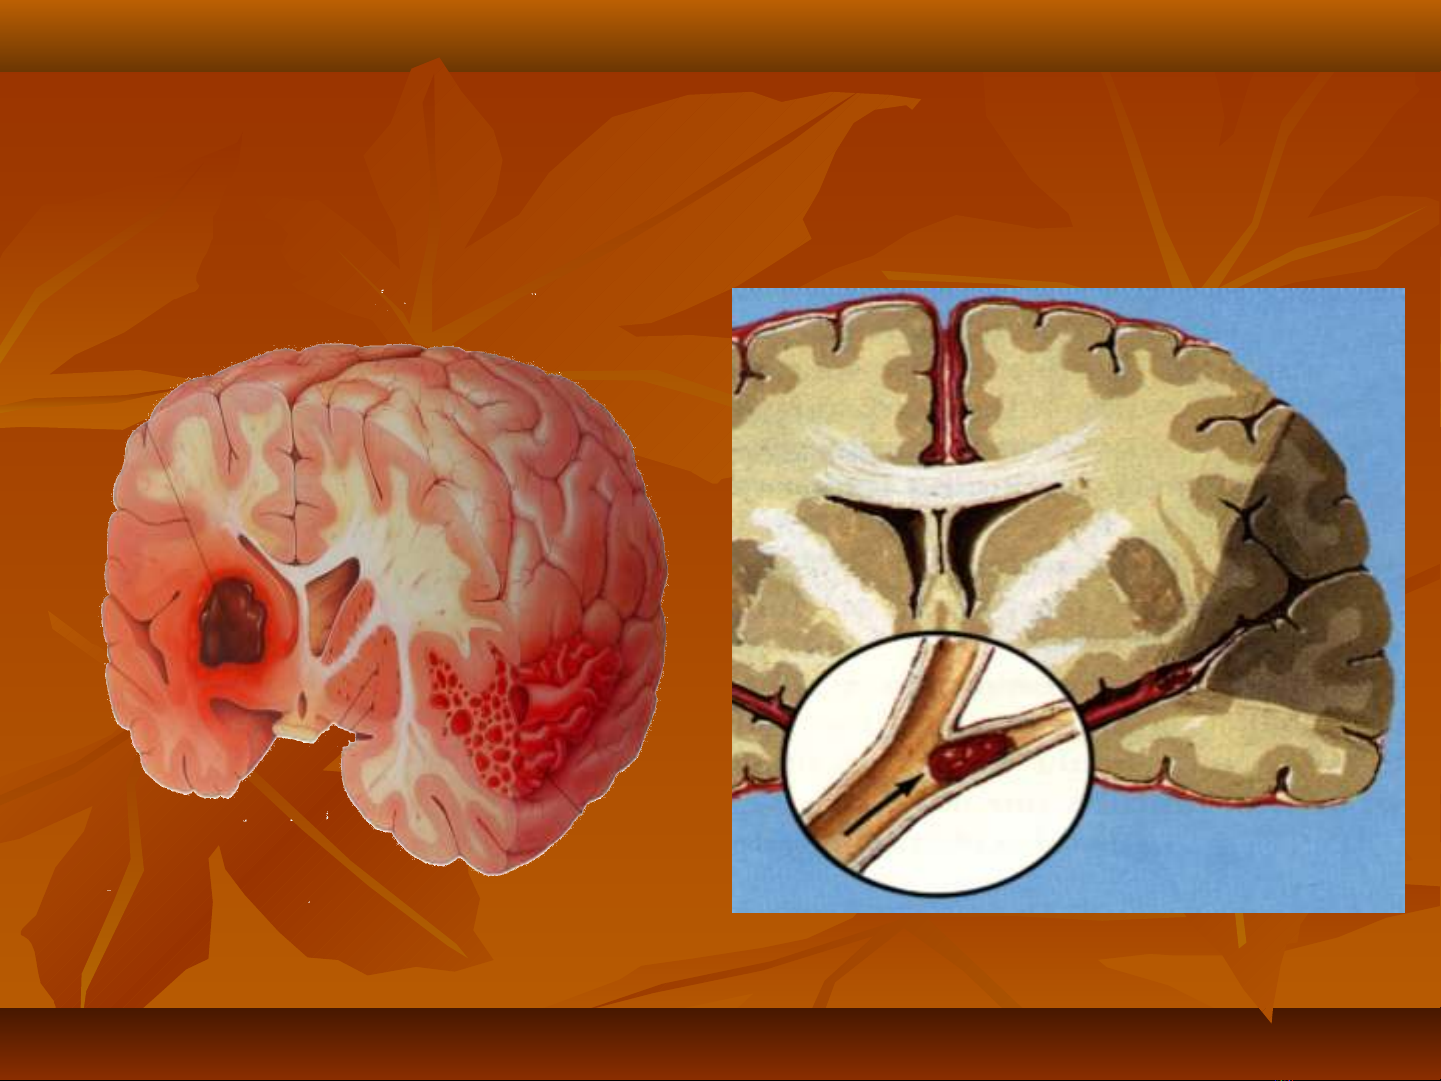

-Xu t huy t não: v m chấ ế ỡ ạ

Xu t huy t não: v m chấ ế ỡ ạ

-Nh i máu não: t c m ch ồ ắ ạ

Nh i máu não: t c m ch ồ ắ ạ